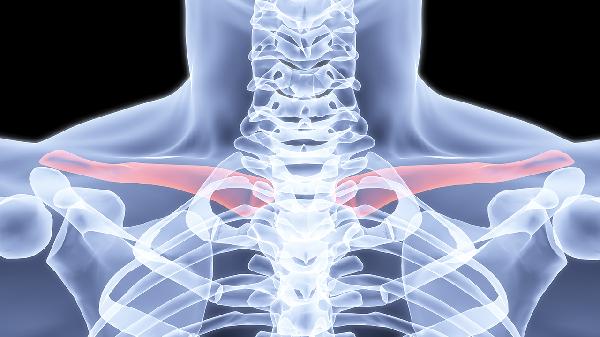

4、胸锁关节紊乱

关节半脱位或退行性变会导致锁骨内侧钝痛,转颈或深呼吸时加剧。塞来昔布胶囊消炎镇痛,手法复位需由专业康复医师操作,日常应避免单侧背包等不对称受力行为。